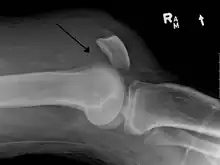

Quadriceps tendon rupture in plain X-ray: Incomplete rupture with haematoma in tendon.